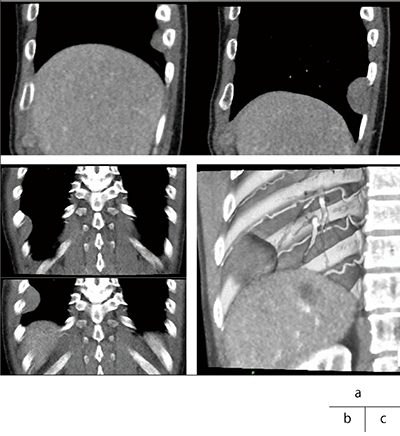

孤立性線維性腫瘍(solitary fibrous tumor:SFT)は胸膜腫瘍であり、画像診断にはCT、MRIが用いられているが、呼吸変動で腫瘍の位置が変位することが認められる。臓側胸膜発生の有茎性の腫瘍であれば肺部分切除にとどめることが可能であるが、壁側胸膜、胸壁、横隔膜あるいは縦隔臓器に接する腫瘍では、それらを含む合併切除が必要になる場合がある。

悪性であれば肺への浸潤や血管との関係も重要である。CTで動態撮影をしたデータにPhyZiodynamicsを用いることでフェーズ数増加、ノイズ軽減につながる。4Dシネの情報から、腫瘍は呼吸性に移動しており臓側胸膜由来の腫瘍が疑われる(図5a、b)。図5cの画像より、腫瘍は血管とは同期しておらず栄養血管はないと考えられる。また、癒着が強いとひきつられるので有茎性の腫瘍であると予測ができる。4Dモーション解析では、カラーマップは腫瘍部位、肺底と同様の分布をしており(図6)、さらにDynamic VOIで解析したグラフを見ても肺と同じ動きを示していることがわかる(図7)。

以上により、胸膜腫瘍に対してPhyZiodynamicsを併用したCT動態撮影は有効であり、腫瘍の質的診断にもつながると言える。

図7 Dynamic VOIにてモーション解析をしたグラフ(上段:腫瘍部位、下段:肺底)

a:velocity b:displacement